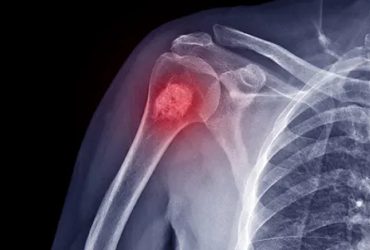

Τα οστά των παιδιών και των εφήβων διαθέτουν μια ειδική περιοχή όπου αναπτύσσεται το οστό που ονομάζεται πλάκα ανάπτυξης. Οι πλάκες ανάπτυξης είναι περιοχές χόνδρου που βρίσκονται κοντά στα άκρα των οστών.

Όταν το παιδί μεγαλώσει πλήρως, οι πλάκες ανάπτυξης κλείνουν και αντικαθίστανται από συμπαγές οστό. Μέχρι να συμβεί αυτό, οι πλάκες ανάπτυξης είναι ασθενέστερες από τους κοντινούς τένοντες και τους συνδέσμους και είναι ευάλωτες σε τραύματα.

Μια ακτινογραφία ενός εφηβικού ποδιού δείχνει την ανοιχτή πλάκα ανάπτυξης του πέλματος.